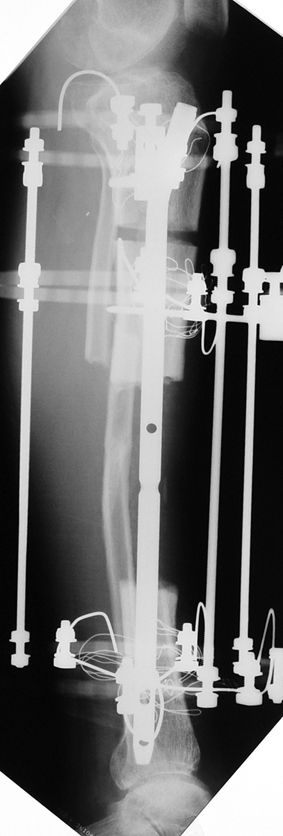

Eksternal fiksatör ile geçen süre (eksternal fiksasyon indeksi), gereken distraksiyon miktarına bağlıdır ve bu süre boyunca bazı komplikasyonlarla karşılaşılabilir. Distraksiyon dönemi sona erdikten sonra, distraksiyon süresinin iki katını aşan konsolidasyon döneminde hastalar eksternal fiksatörü zorlukla tolere edebilirler. Yeterli konsolidasyon sağlanmadan eksternal fiksatör çıkartılırsa ise kırıklar, deformite ve kısalık oluşabilir. Hastanın fiksatör ile birlikte geçirdiği sürenin azaltılması ve böylece hasta konforunun ve aktivite düzeyinin arttırılması için intramedüller çivi üzerinden uzatma yöntemi uygulanmaktadır. Bu yöntemde distraksiyon dönemi sona erdiğinde kemiğin içindeki çivi statik olarak kilitlenmekte ve eksternal fiksatör çıkartılmaktadır. Stabilizasyon intramedüller çivi tarafından sağlandıktan sonra konsolidasyon dönemi gerçekleşmektedir. Bu şekilde hem eksternal fiksatörün uzun süre kalmasından hem de erken çıkartılmasından kaynaklanan komplikasyonların önüne geçilmektedir.